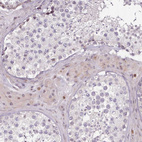

Immunohistochemical staining of human testis shows weak nuclear positivity in subset of Leydig cells.